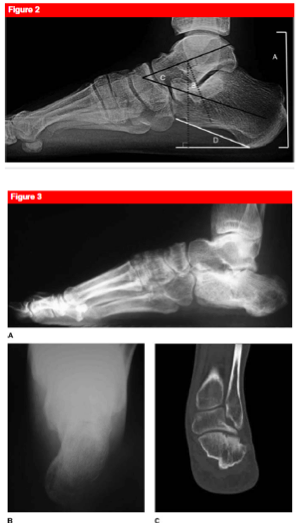

What are the typical radiographic measurements of a calcaneus fracture

What is the sander’s classification of calcaneus fractures